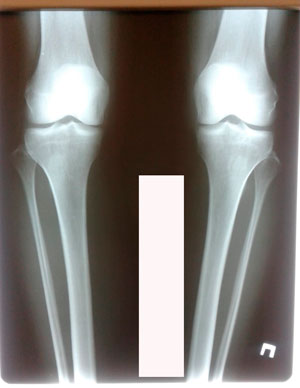

Исходник - 40 лет

Диагноз: варусная деформация голеней + Ротация с обеих сторон.

Дата операции - 09.07.2020

перед крутками